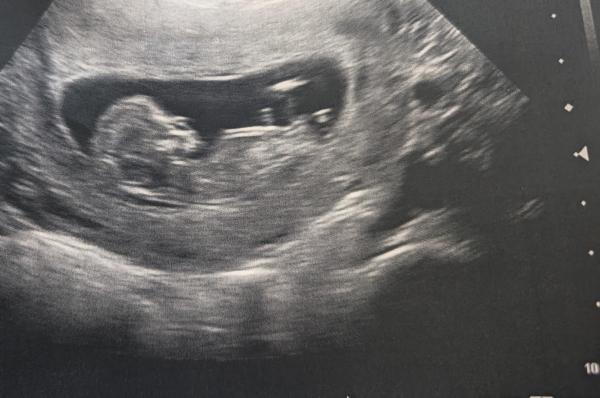

Hallo ihr Lieben, ist nicht das beste Bild und nun auch schon ne Weile her... Was meint ihr?  Liebe Grüße  Tatjana

Bild zu NUB - Forum für März - Mamis

Huhu Tatjana, würde da auf ein Mädchen Tippen, weil er doch sehr nah zusammen verläuft. Hast du denn mittlerweile ein Outing? Oder eine Tendenz gesagt bekommen?  GLG  Cleo

Huhu, danke für Deine Antwort. 🙂 Nein, hab noch kein Outing. In 3 Wochen hab ich wieder Termin, da dürfen auch meine beiden Jungs mit zum Ultraschall. Beim letzten Ultraschall hat Babychen so ganz leicht nur die Beine geöffnet und da konnten wir keinen Penis entdecken. 😅😉🫣   Ich hab den NUB über so ne Seite professionell bestimmen lassen, aber da wurde halt noch der obere Zipfel (der m. E. garnicht mehr dazu gehört) "mitgezählt" und deswegen zu Junge tendiert.    Mir ist es wirklich egal, ich bin nur langsam doch etwas neugierig und hibbelig, deshalb mein Post. Ich hoffe es schauen noch ein paar mit drauf. 🙂🙃

Ach witzig. Icb hätte jetzt gedacht, dass der Nub doch echt sehr eng beieinander liegt und hätte es als Gabelung gedeutet!  Vorallem verläuft er ja da doch echt sehr parallel zur Wirbelsäule.  Also ich dachte das mittlerweile besser sehen zu können, nachdem ich mir gefühlt 100 Bilder angeguckt habe um herauszufinden was der Nub meines kleinen Krümels sagen möchte aber nichts passt 😄